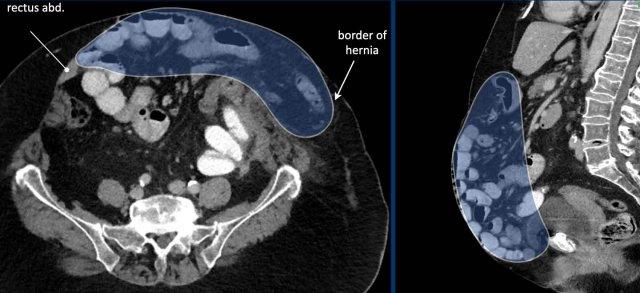

Hình ảnh

Ở bệnh nhân này, mức độ mất vùng chứa > 20% và cần áp dụng các chiến lược bổ sung để tăng dung tích và độ giãn nở của khoang bụng.

Ở bệnh nhân này với khối thoát vị lớn, các số đo như sau:

- Thể tích túi thoát vị (HSV) = (274 x 71 x 304 mm x 0,52) x 10-6 = 3,1 lít.

- Thể tích khoang bụng (ACV) = (251 x 131 x 342 mm x 0,52) x 10-6 = 5,8 lít.

- Tổng thể tích phúc mạc (TPV) = ACV + HSV = 3,1 + 5,8 = 8,9 lít.

Mức độ mất vùng chứa trong trường hợp này là thể tích túi thoát vị chia cho tổng thể tích khoang phúc mạc:

3,1 : 8,9 = 35%.

Con số này vượt xa ngưỡng 20% và có nghĩa là nguy cơ biến chứng trong và sau phẫu thuật tái tạo thành bụng đơn thuần là rất cao.